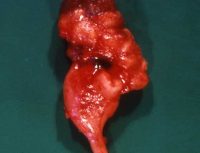

Die Refluxnephropathie ist von einer fortschreitenden Destruktion des Nierenparenchyms geprägt (Abbildung 7). Die pathologischen Veränderungen sind dabei abhängig vom Grad des Refluxes und oder der bakteriellen Infektion.

Die Nieren sind klein und haben ein Gewicht von ca. 40g. Die Nierenoberfläche ist diffus-höckrig. Refluxnarben finden sich an den Polen und der Mitte des Organs. Auf der Schnittfläche zeigt sich das Parenchym reduziert, z.T. mit abgeflachten Papillen und Bildung von Exkavationen bzw. Rezessi (Abbildung 7,8,9)

Beispiele Nieren mit ausgeprägter Refluxnephropathie.